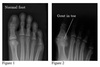

What X-ray changes are seen in psoriatic arthritis? (3)

- may show a combination of erosions and new bone formation - periostitis - 'pencil-in-cup' appearance in advanced disease